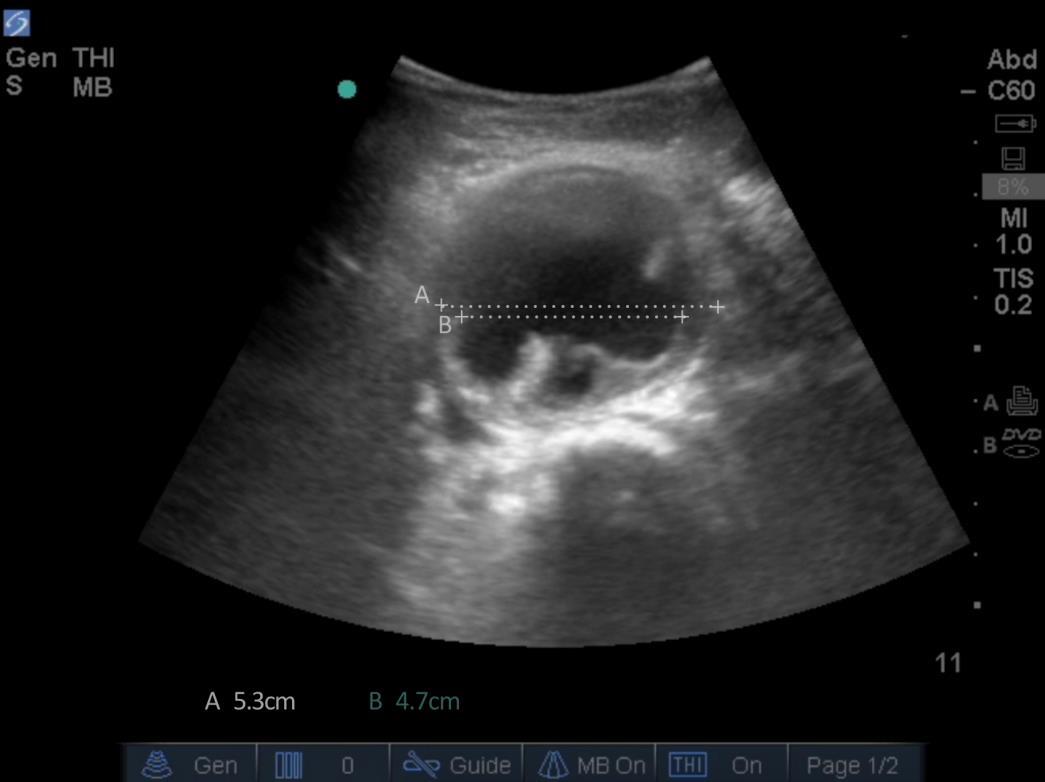

Aorta Measurement of Lumen Image